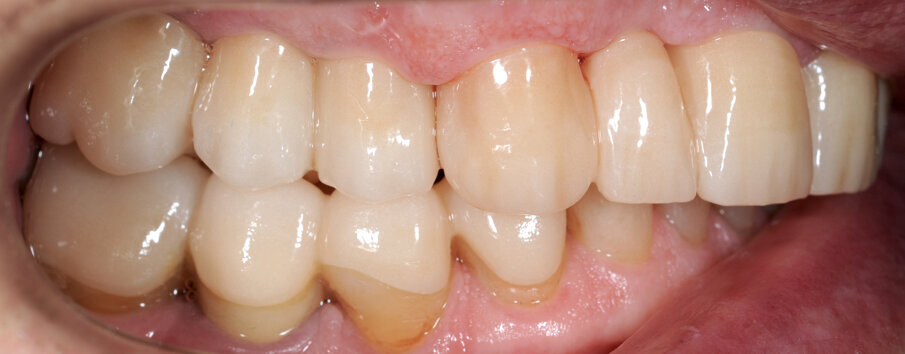

Il fresato ottenuto è poi riportato su articolatore Reference SL – già opportunamente programmato – e viene dall’Odontotecnico competente più precisamente funzionalizzato secondo i criteri della programmazione funzionale sequenziale, evidenziando con cere colorate i rapporti di centrica, le funzioni di mediotrusiva e protrusiva e le protezioni retrusive. I monconi sfilabili consentono la modellazione della sequenzialità mediotrusiva con la guida incisale indicata dalla registrazione axiografica (blu) (Figg. 34-37). La ceratura sequenziale è ora scansita con Sirona InEos X5 su Exocad, ed il modellato viene ricontrollato al CAD per spessori, connessioni e morfologia, e nella regolazione degli offsets per la ripreparazione dei monconi, ed è inviato al CAM per la fresatura dei II provvisori in Bredent breCAM.multicom, un PMMA con microriempitivo ceramico ad alta stabilità, su Dental Plus 5 Axis Milling Machine. La rifinitura dei monconi è seguita da ribasatura dei II provvisori in TRP - previo isolamento di tutte le superfici funzionali - e gli stessi sono poi rifiniti e lucidati. I soli elementi 3.3, 4.2 e 4.3 sono rimodellati in regione incisale con addictions in composito, secondo la morfologia studiata in ceratura. La consegna conferma la buona integrazione dei manufatti dal punto di vista estetico, occlusale, articolare e neuromuscolare, con controllo occlusale conforme al progetto (Figg. 38-42).

Il paziente utilizza questi secondi provvisori per otto settimane, durante le quali conferma la buona integrazione dei restauri e la soddisfacente funzione occlusale. Ciò è verificato con l’esecuzione di una nuova axiografia elettronica che già a due settimane dalla consegna evidenzia una buona risposta muscolare al nuovo design occlusale ed alla nuova postura mandibolare in TRP (Figg. 43-46). Provvediamo infine alle impronte per la costruzione dei manufatti definitivi in Zirconia-ceramica. I modelli sono scansiti in laboratorio con inEos X5 (Dentsply Sirona) su exocad (Figg. 47-49), ed una seconda scansione viene eseguita con i provvisori del Paziente posizionati sui modelli (Figg. 50-52). Il CAD consente di eseguire un matching fra le due scansioni, per cui i secondi provvisori utilizzati in TRP, con funzione occlusale sequenziale già completamente programmata, sono utilizzati per definire le morfologie dentali definitive di tutti gli elementi da restaurare (Figg. 53, 54) secondo il rapporto intermascellare definito (Figg. 55-58). Si esegue quindi fresatura al CAM della protesi definitiva in zirconia (Figg. 59, 60), la stratificazione e finitura ed infine la consegna al Paziente con cementazione in Panavia V5 (Figg. 61-65).